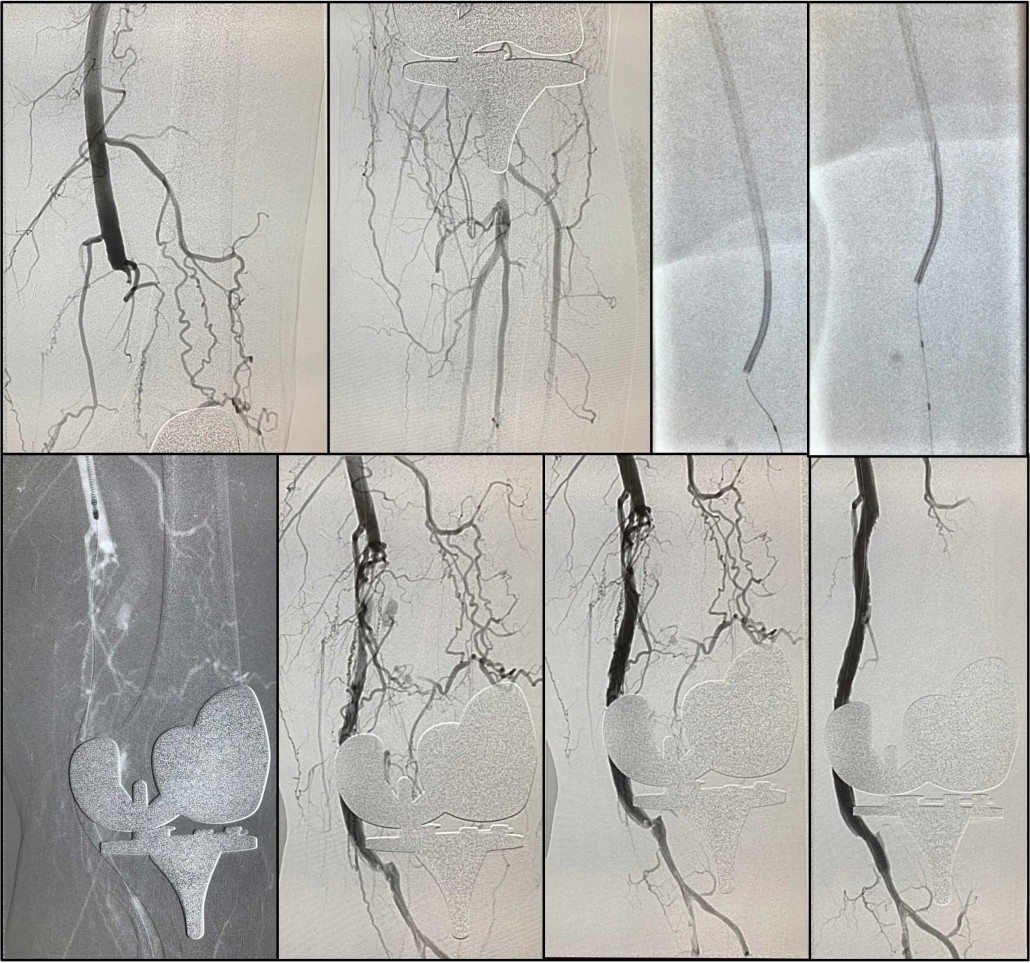

Rescate de bypass obstruido con Rotarex

Trombolisis (fibrinolisis) urgente con Angiojet por trombosis de stent

Trombectomía bypass obstruido con Rotarex